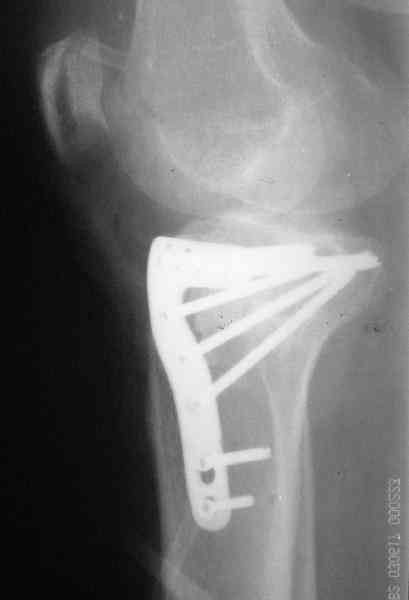

Re: Застарелый перелом 41С3

Уважаемый Абдурашид. Если нет противопоказаний , то из оперативных способов, я бы рекомендовал следующие: Полное замещение наружного мыщелка аллотрансплантатом либо открытая репозиция с элевацией и замещение дефекта ауто или аллокостью. В Ваших условиях , я бы рекомендовал второй способ. Во-время элевации необходимо разъединить фрагменты со стороны сустава ( надсечь скальпелем по линиям перелома, а затем тонким остеотомом их разъединить. При помощи долота произвести неполную остеотомию ( захватите не менее 1,5 - 2 см губчатой кости и поднять фрагменты, визуально отрепонировать и фиксировать 2-3 спицами. Дефект заместить костным ауто или аллатрансплантатом. Окончательная стабилизация пластиной ( лучше с угловой стабильностью, либо АВФ - позволит спокойно устранить угловую деформацию.

Недавно поступила больная через 1,5- 2 месяца.